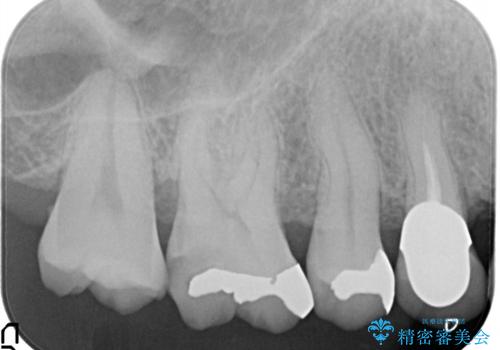

セラミッククラウンによるむし歯治療

- 他院で入れたセラミックインレーがかけたことを主訴に来院されました。

他の部位にもむし歯を認めたため、優先度の高い歯から治療を行っております。

咬合力が強くかかる部分には欠けるリスクのほとんどない金属を用いることが最良ですが審美性に劣ります。

今回は白い材料での修復を希望されたため、欠けるリスクが高いセラミックインレーは避け、セラミッククラウンにて治療を行いました。